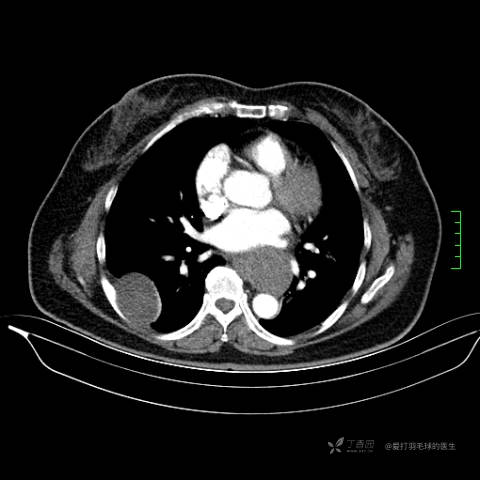

主诉:患者因反复右侧腰痛伴右下肢麻木2年余入院。

简要病史:自诉右甲状腺功能亢进症多年,规律服药,平素多有心悸、胸闷、活动后明显。既往腰椎椎管内肿瘤切除术。